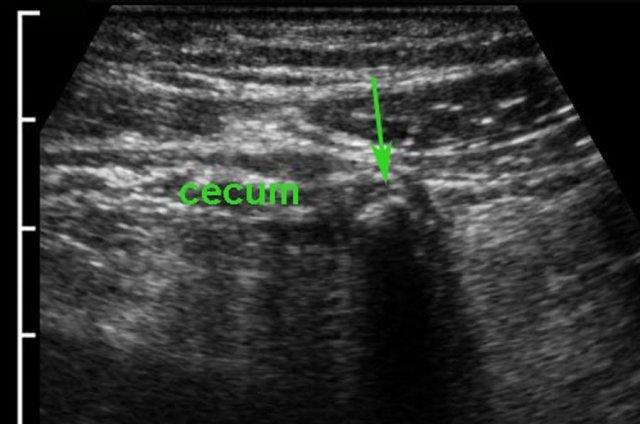

Viêm ruột thừa sau manh tràng

Ruột thừa thường được tìm thấy tại vị trí đau nhất khi ấn.

Trong viêm ruột thừa sau manh tràng (mũi tên), manh tràng thường bị đẩy về phía trong bởi đầu dò siêu âm, khiến ruột thừa (mũi tên) có vẻ nằm ở phía bên ngoài manh tràng thay vì phía sau nó.

Một khả năng khác để quan sát ruột thừa trong viêm ruột thừa sau manh tràng là đặt đầu dò ở vùng hông phải, nhờ đó tránh được manh tràng chứa đầy hơi và phân.

Một mẹo khác trong viêm ruột thừa sau manh tràng là dùng tay trái đẩy ruột thừa đang viêm (mũi tên) về phía đầu dò.

Để tìm ruột thừa, trước tiên có thể hữu ích khi xác định van hồi manh tràng (xem thêm Siêu âm đường tiêu hóa: giải phẫu bình thường).

Gốc ruột thừa thường được tìm thấy cách đó 3 cm về phía đuôi, nơi nó xuất phát từ cực manh tràng ở mặt trong.